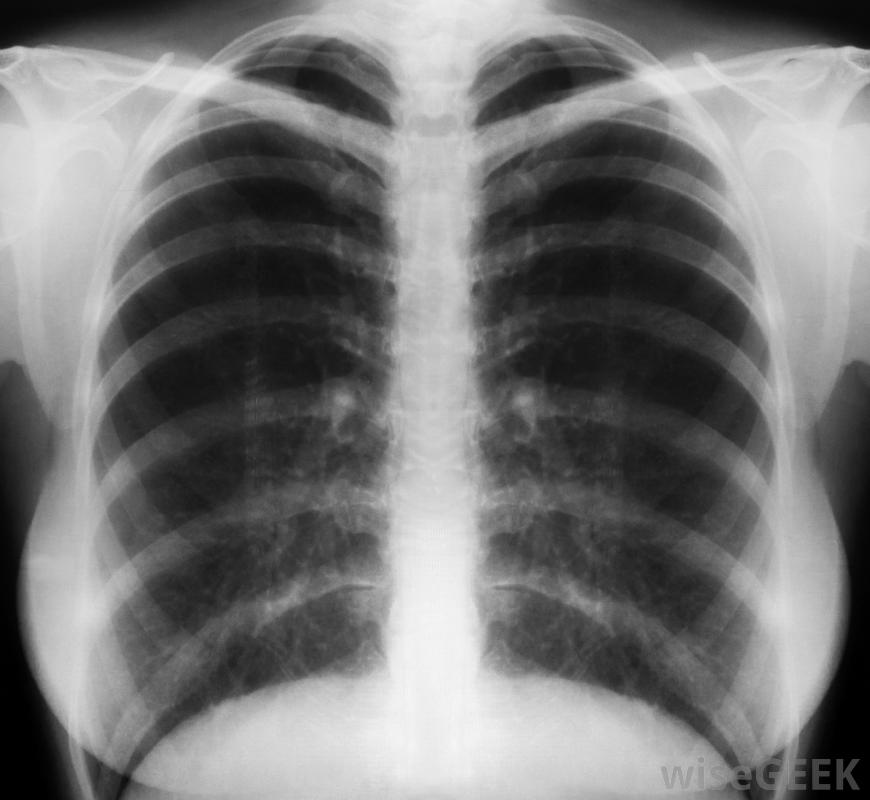

,毛细支气管炎是支气管内膜的炎症,细支气管炎是细支气管或肺部小通道的炎症。这种病毒感染在秋季和冬季会影响儿童和婴儿。虽然通常不需要治疗,但在孩子病情严重的情况下,可以服用抗病毒药物。患有毛细支气管炎的儿童可能会出现发烧、喘息或呼吸急促的症状。通常通过检测患儿的鼻液和进行胸部x光检查来确认诊断。

与其他呼吸系统疾病一样,肺炎是由肺部炎症引起的。呼吸急促、发热和咳嗽等症状都可以作为肺炎的征兆。诊断可通过多种检查来进行,包括全血细胞计数(CBC)、胸部CT扫描和痰培养试验,严重咳嗽时排出的粘液样物质。一些肺炎需要住院治疗,而较轻的病例可能只需要使用抗生素。

SARS患者可能会出现呕吐等症状,腹泻、流鼻涕和喉咙痛。用于诊断SARS的检查包括胸部CT扫描、全血细胞计数(CBC)和胸部x光片。SARS的治疗包括隔离住院、使用抗生素和抗病毒药物以及类固醇以减少肺部炎症。严重者,除了机械通气或人工呼吸支持外,还可使用氧气。与SARS相关的并发症包括呼吸、心脏和,呼吸急促是冠状病毒引起肺炎的指标。